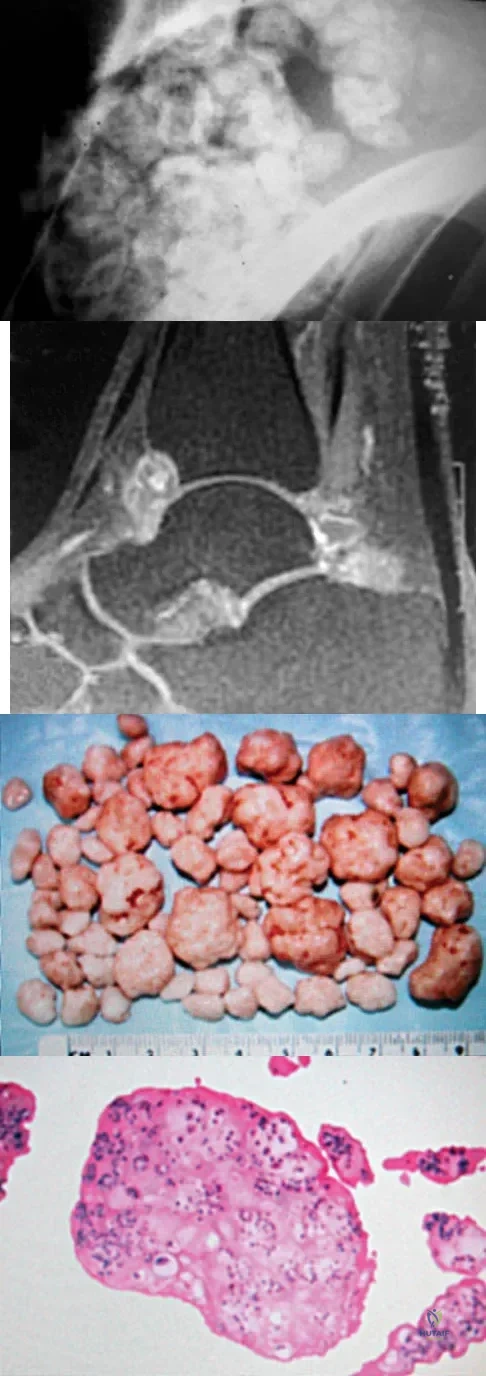

A 40-year-old man has a painful mass on his anterior ankle joint with limited range of motion. A radiograph, MRI scan, a gross specimen, and a hematoxylin/eosin biopsy specimen are shown in Figures 5a through 5d. What is the most likely diagnosis?

Explanation